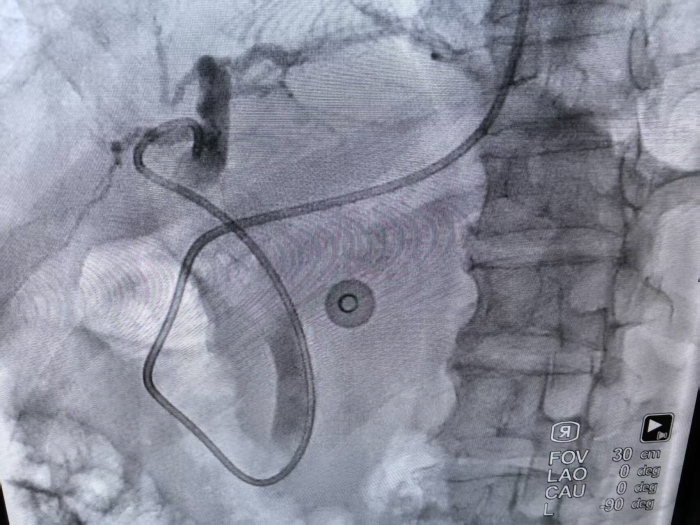

置入胆管引流管

术后,患者胆红素水平显著下降,感染指标同步回落,为后续治疗奠定了基础;综合外科团队则全程关注,针对患者病情变化制定个性化手术预案,随时准备应对可能出现的外科急危情况,为患者平安护航。